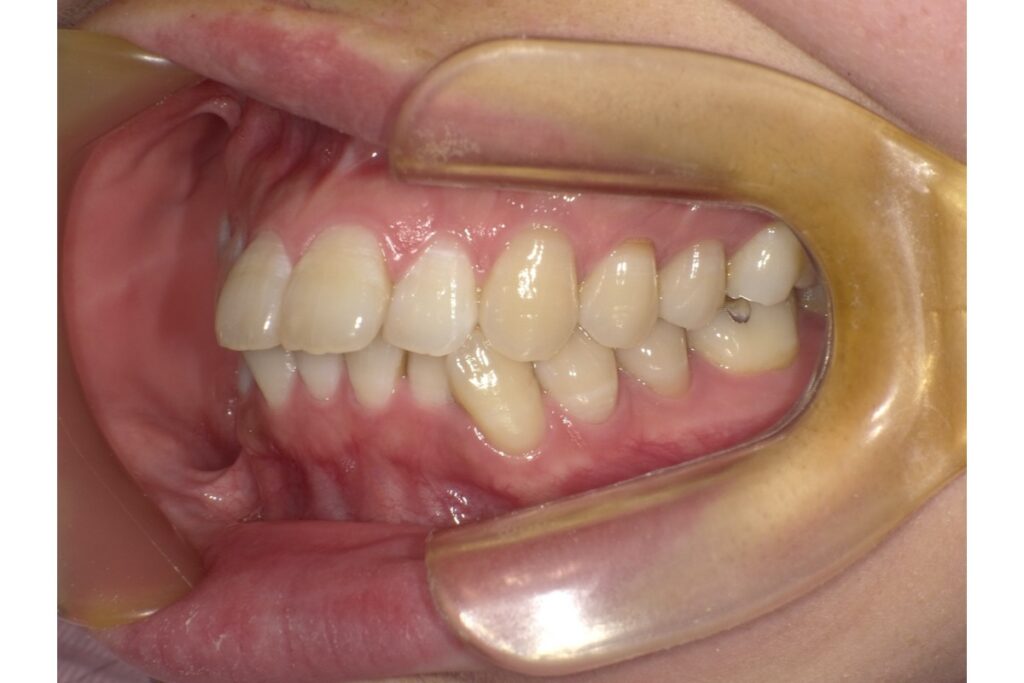

左下5番目の歯の治療前後の歯ぐきの位置を比較すると、歯茎が下がっているのがわかります。

「歯茎が下がる」とは、歯を支えている歯茎や骨が後退し、歯の根元が見えてしまう状態を指します。専門的には「歯肉退縮」と呼ばれ、以下のような見た目や症状が現れます。